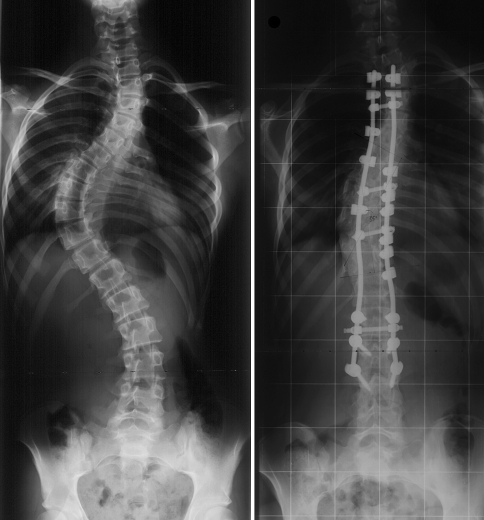

Coronal and axial plane correction

The average preoperative Cobb angle of the major curve was 60° ± 20°. The mean flexibility of the major curve was 42 ± 13%. Immediate postoperative major curve correction averaged 66 ± 13% (Fig. 5). The reduction of the Cobb angle was significant (P < 0.0001). The average loss of correction of the major curve between the early postoperative assessment and latest follow-up was 3.5° ± 1.4°. No pseudarthrosis was noted. Coronal plane changes of the upper thoracic, main thoracic and lumbar curves are reported in Table 2.

Fig. 5.

Anteroposterior radiographs, preoperative and at 30 months postoperative, of a girl with Lenke type 2 scoliosis, operated at the age of 15 years. Six sublaminar UCs were used to instrument the concavity of the main thoracic curve. The posteromedial translation technique achieved a 65% correction of the major curve